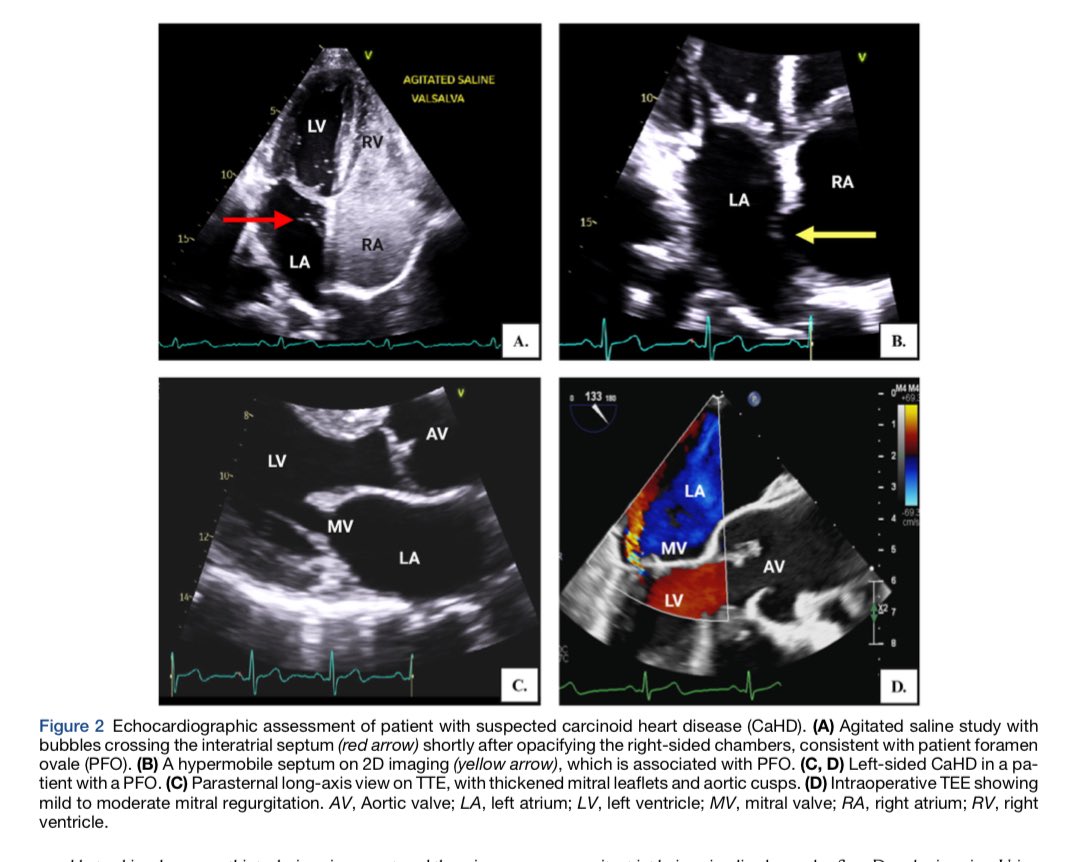

🔵 Echocardiographic Evaluation of Carcinoid Heart Disease @JournalASEcho #Cardiology #CardioEd #echofirst #FOAMed